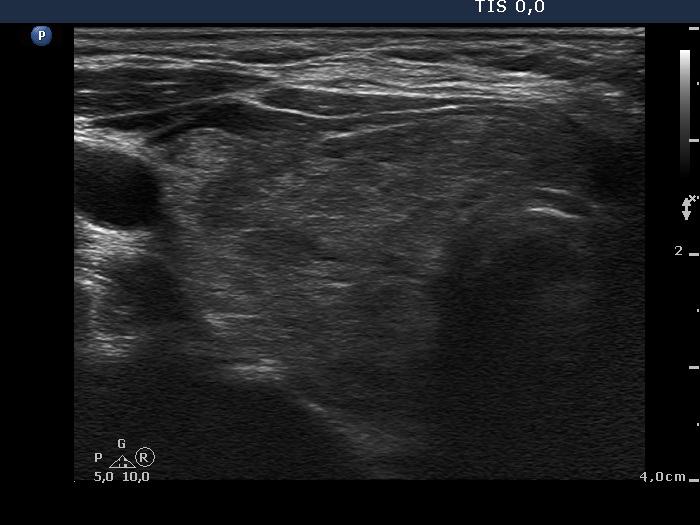

Second examination - 3 years after surgery (2nd row of images)

Comments.Clinical data: the thyroid function of the patient was regularly checked. She was euthyroid until the last blood test. She had no complaints except for a 5 kg gain in weight.

Palpation: the right thyroid was enlarged.

Results of blood tests: subclinical hypothyroidism (TSH 5.18 mU/L, FT4 12.7 pM/L).

Ultrasonography: the right thyroid was minimally-moderately hypoechogenic and enlarged and contained several hypoechogenic areas. The resected left lobe was moderately hypoechogenic.A replacement therapy with 50 microgram levothyroxin was started.

Before surgery the thyroids presented unequivocal signs of lymphocytic thyroiditis: the left thyroid was moderately hypoechogenic while the right displayed hypoechogenic spots within an echonormal background.

Three years after surgery the right thyroid became enlarged because it had to take over the hormon production of the resected left thyroid.